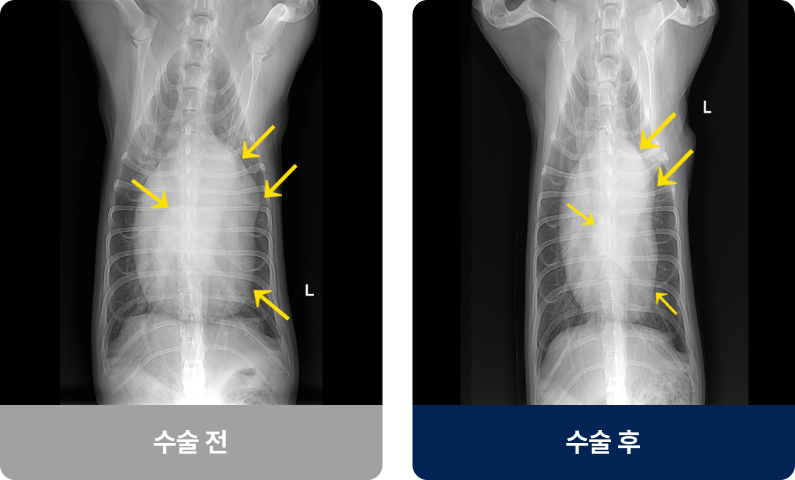

심장을 둘러싼 얇은 막(심낭)에 체액이나 혈액이 비정상적으로 고이는 상태로, 쌓인 액체가 심장을 압박해 심장이 제 기능을 하지 못하게 되면 저혈압이나 쇼크로 이어질 수 있습니다. 주로 종양, 염증, 외상 등으로 발생하며 갑작스러운 기력 저하나 호흡곤란을 보입니다.